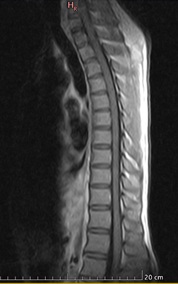

On neuroimaging, MRI cervico-thoracic spine showed T2 hyperintense lesion extending from the lower cervical to the mid-thoracic cord with minimal cord expansion, with no post-contrast enhancement, likely due to inflammatory demyelinating aetiology. (Figure 1 & 2) MRI Brain with contrast done in this patient, was reported as an essentially unremarkable study with no evidence of demyelinating plaques or any other significant abnormality (Figure 3).

Figure 2: T1 with contrast sagittal view shows no post contrast enhancement.

Transverse myelitis is an initial presentation mainly in adults who are seropositive for MOG-AD. It is a severe, disabling condition, and with the help of antibody assessment for NMOSD and MOG, we are able to identify the causes of transverse myelitis. MOG-IgG-associated myelitis presents as acute flaccid myelitis. MOG-AD transverse myelitis is mostly longitudinally extensive (LETM). As in our case, MRI dorsolumbar spine showed a longitudinally extensive lesion extending from the lower cervical to the mid-thoracic region. It showed no post-contrast enhancement as compared to AQP4-IgG seropositive myelitis. Deep grey matter lesions are more common in MOG-IgG myelitis [7]. It can also be associated with optic neuritis and brainstem encephalitis. We can differentiate MOG-AD from NMOSD and MS, although there are few clinical and radiological similarities between MOG-AD and NMOSD but can easily differentiate from MS. Silent lesions which are commonly found in MS are absent in MOGAD [1]. MOGAD has the greatest predilection for conus medullaris resulting in sphincter involvement and bladder dysfunction [8].